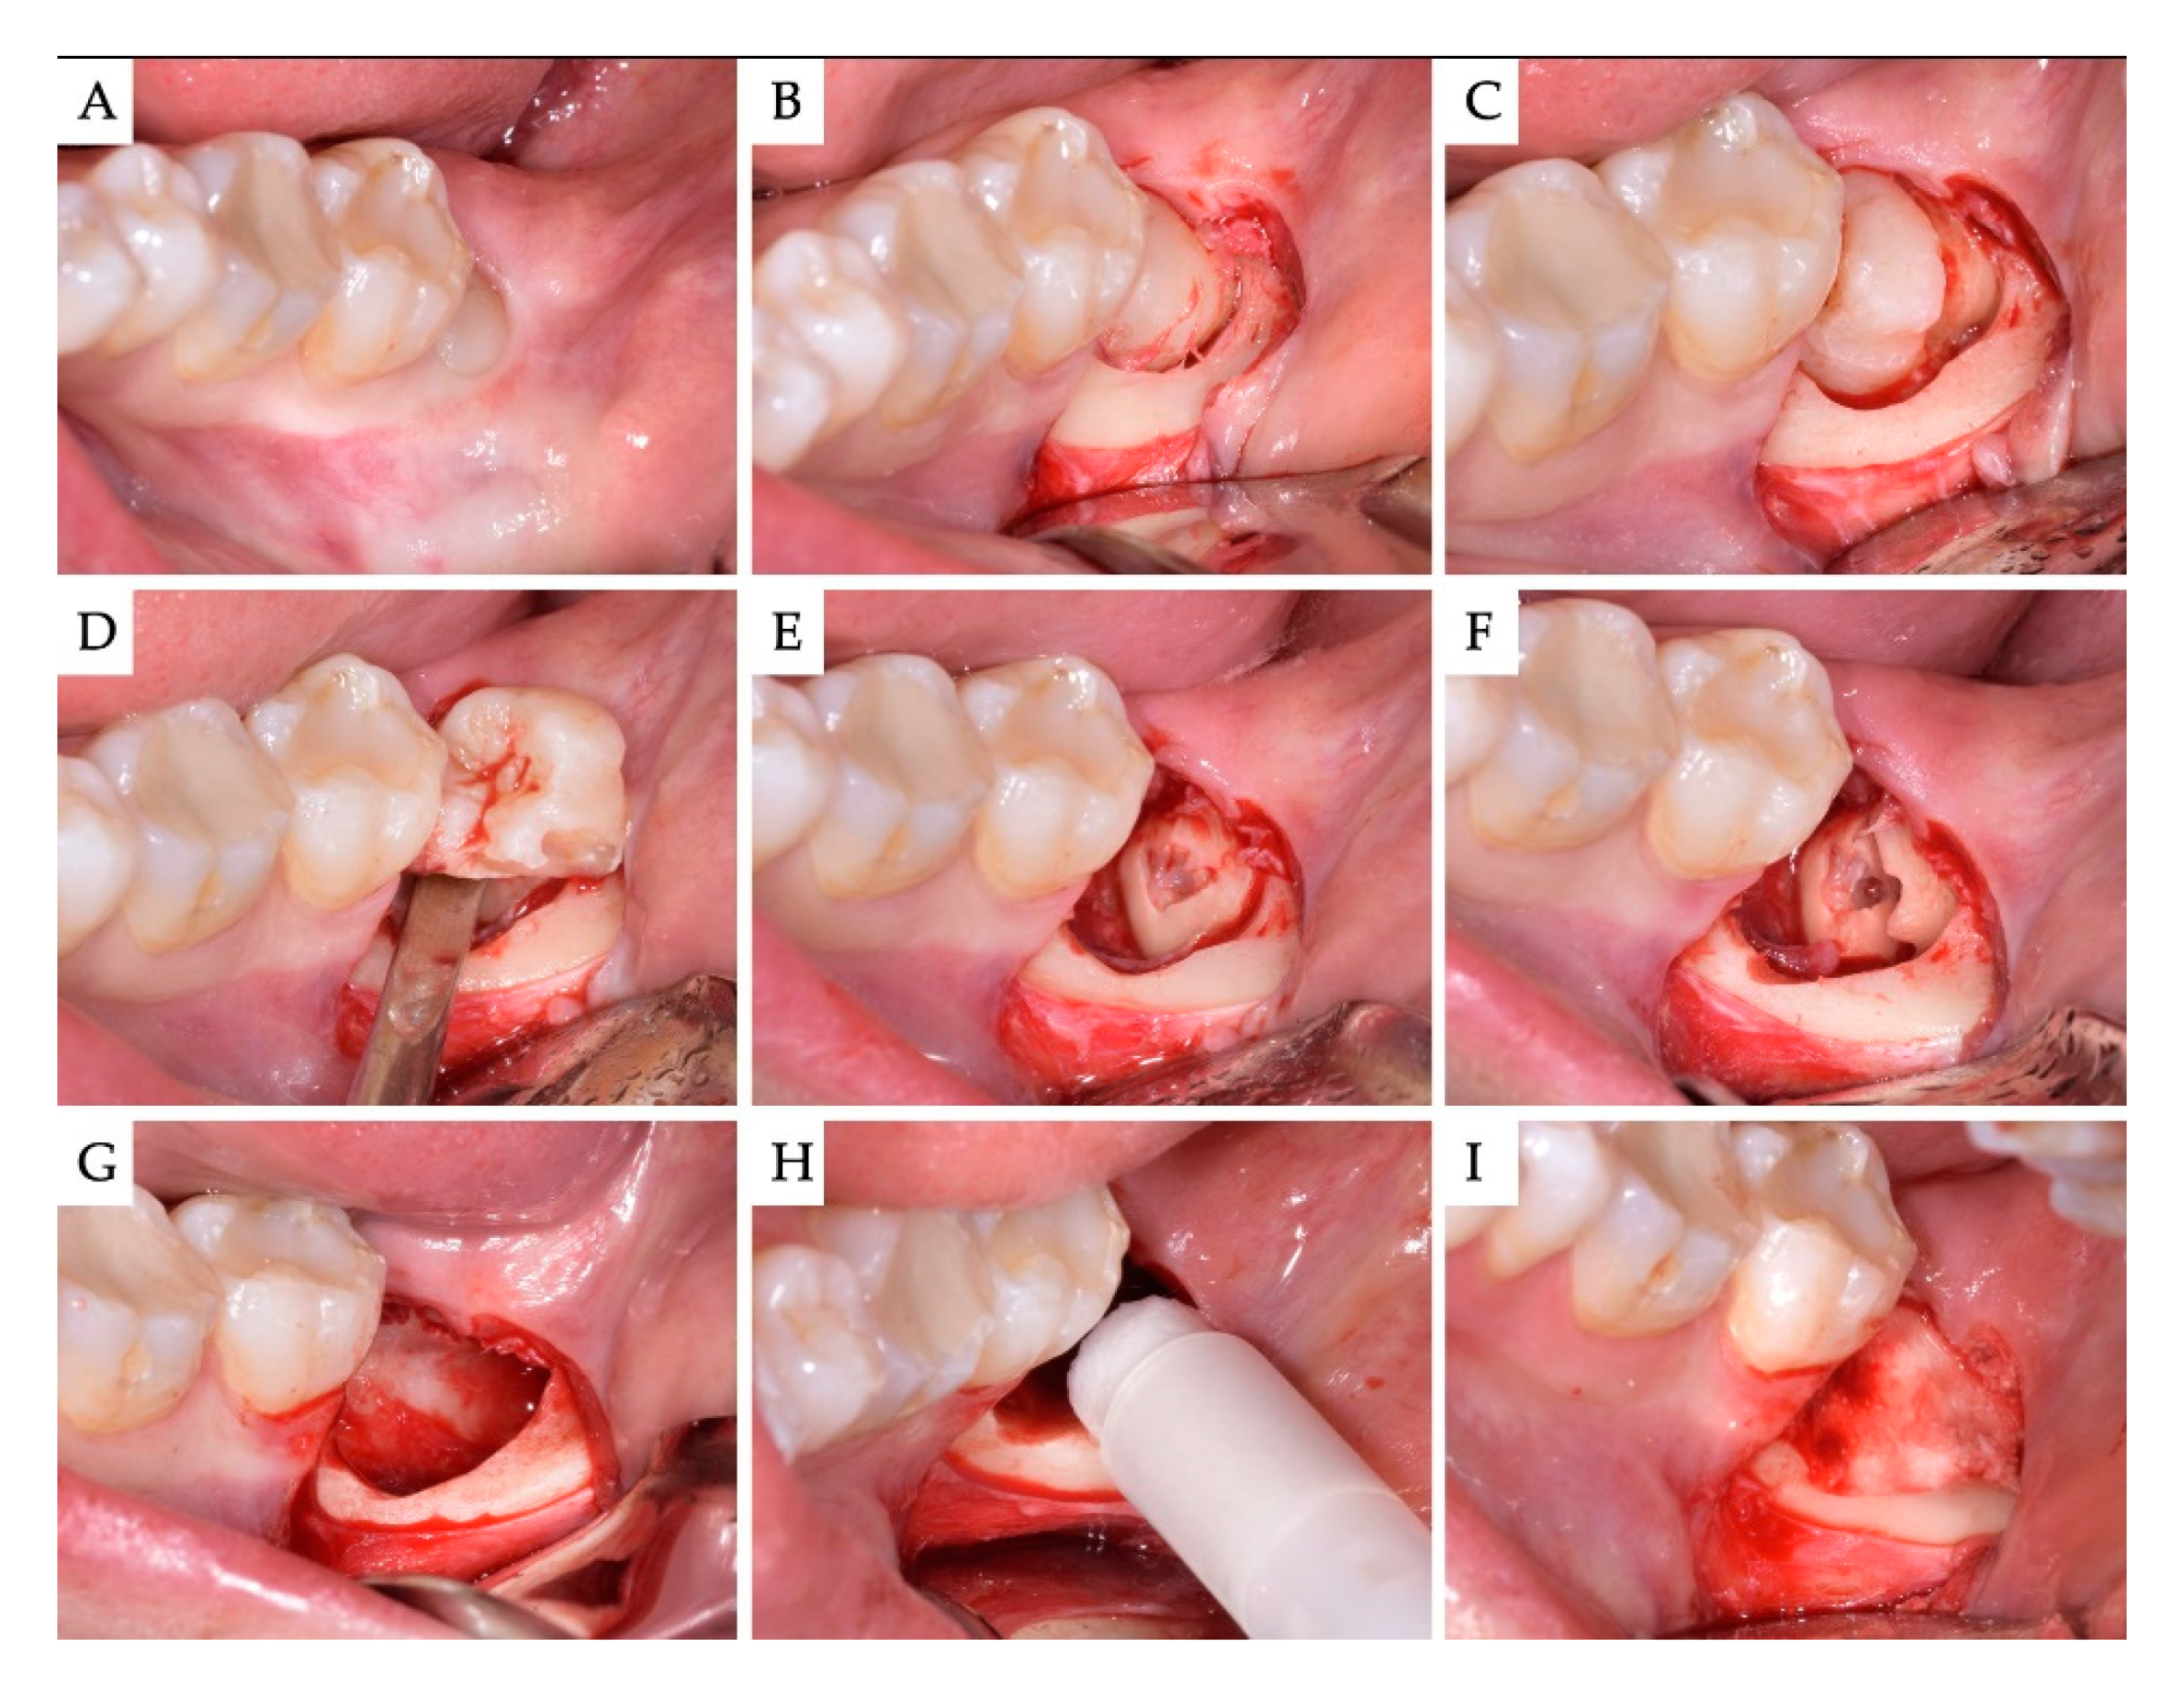

3. Results